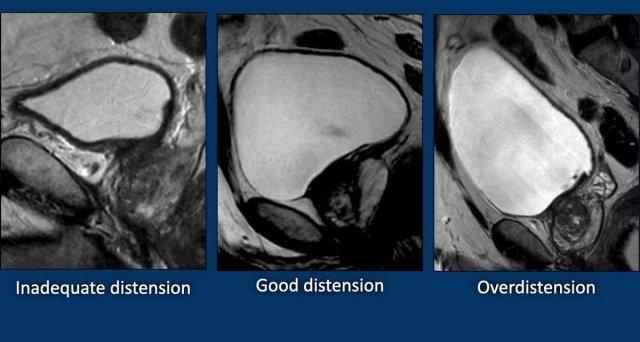

Độ căng bàng quang

Độ căng bàng quang tối ưu đóng vai trò then chốt trong việc phân giai đoạn khối u chính xác.

Tất cả các hình ảnh dưới đây đều là bàng quang bình thường.

- Căng không đủ

thành bàng quang có hình ảnh dày và không đều, có thể dẫn đến chẩn đoán nhầm hoặc đánh giá quá mức giai đoạn khối u. - Căng bàng quang đúng mức.

Hướng dẫn bệnh nhân đi tiểu trước khi chụp 1–2 giờ hoặc uống 500–1000 ml nước trong vòng 30 phút trước khi thực hiện thủ thuật, tùy theo khả năng dung nạp của bệnh nhân.

Hình dạng vòm bàng quang lồi ra ngoài gợi ý độ căng bàng quang tối ưu (2). - Căng quá mức.

Tình trạng này có thể gây xảo ảnh do chuyển động liên quan đến khó chịu và có thể che khuất mức độ lan rộng của ung thư bàng quang.